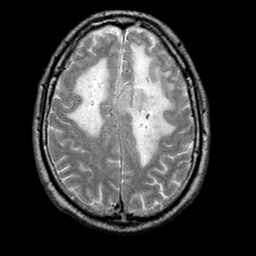

Meningioma, MR Study #1 -- Slice #14

[Home][Help][Clinical] Slice 14